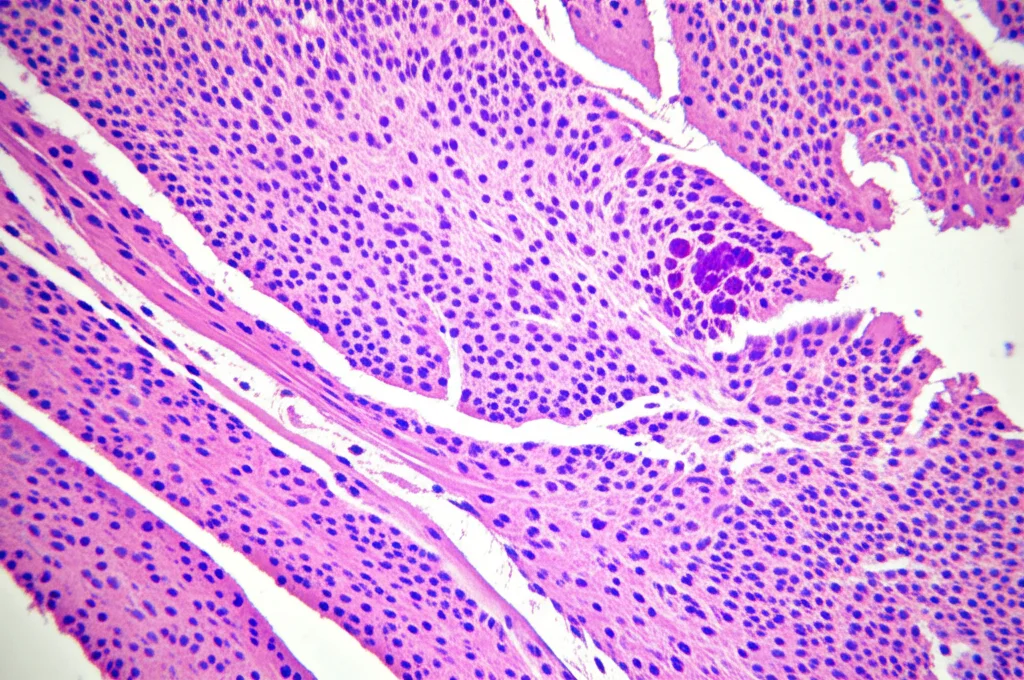

Per dare ancora più solidità ai nostri sospetti, siamo passati al laboratorio, usando un modello animale di BPCO: topolini esposti al fumo di sigaretta e a lipopolisaccaride (LPS) per mimare la malattia umana.

Nei polmoni di questi topolini “BPCO”, abbiamo misurato l’espressione di BPIFB4 e delle proteine chiave della via PI3K/AKT. I risultati? Proprio come suggerito dai dati umani e bioinformatici:

- L’espressione di BPIFB4 (sia mRNA che proteina) era nettamente diminuita nei topi BPCO rispetto ai controlli.

- Al contrario, l’espressione delle forme attivate (fosforilate) di PI3K (p-PI3K) e AKT1 (p-AKT1) era significativamente aumentata nei topi BPCO.

Questo indica che nei polmoni affetti da BPCO (almeno nel modello murino), c’è meno BPIFB4 e la via di segnalazione PI3K/AKT è iperattiva. Bingo! Sembra proprio che BPIFB4 possa influenzare la BPCO agendo su questa via.